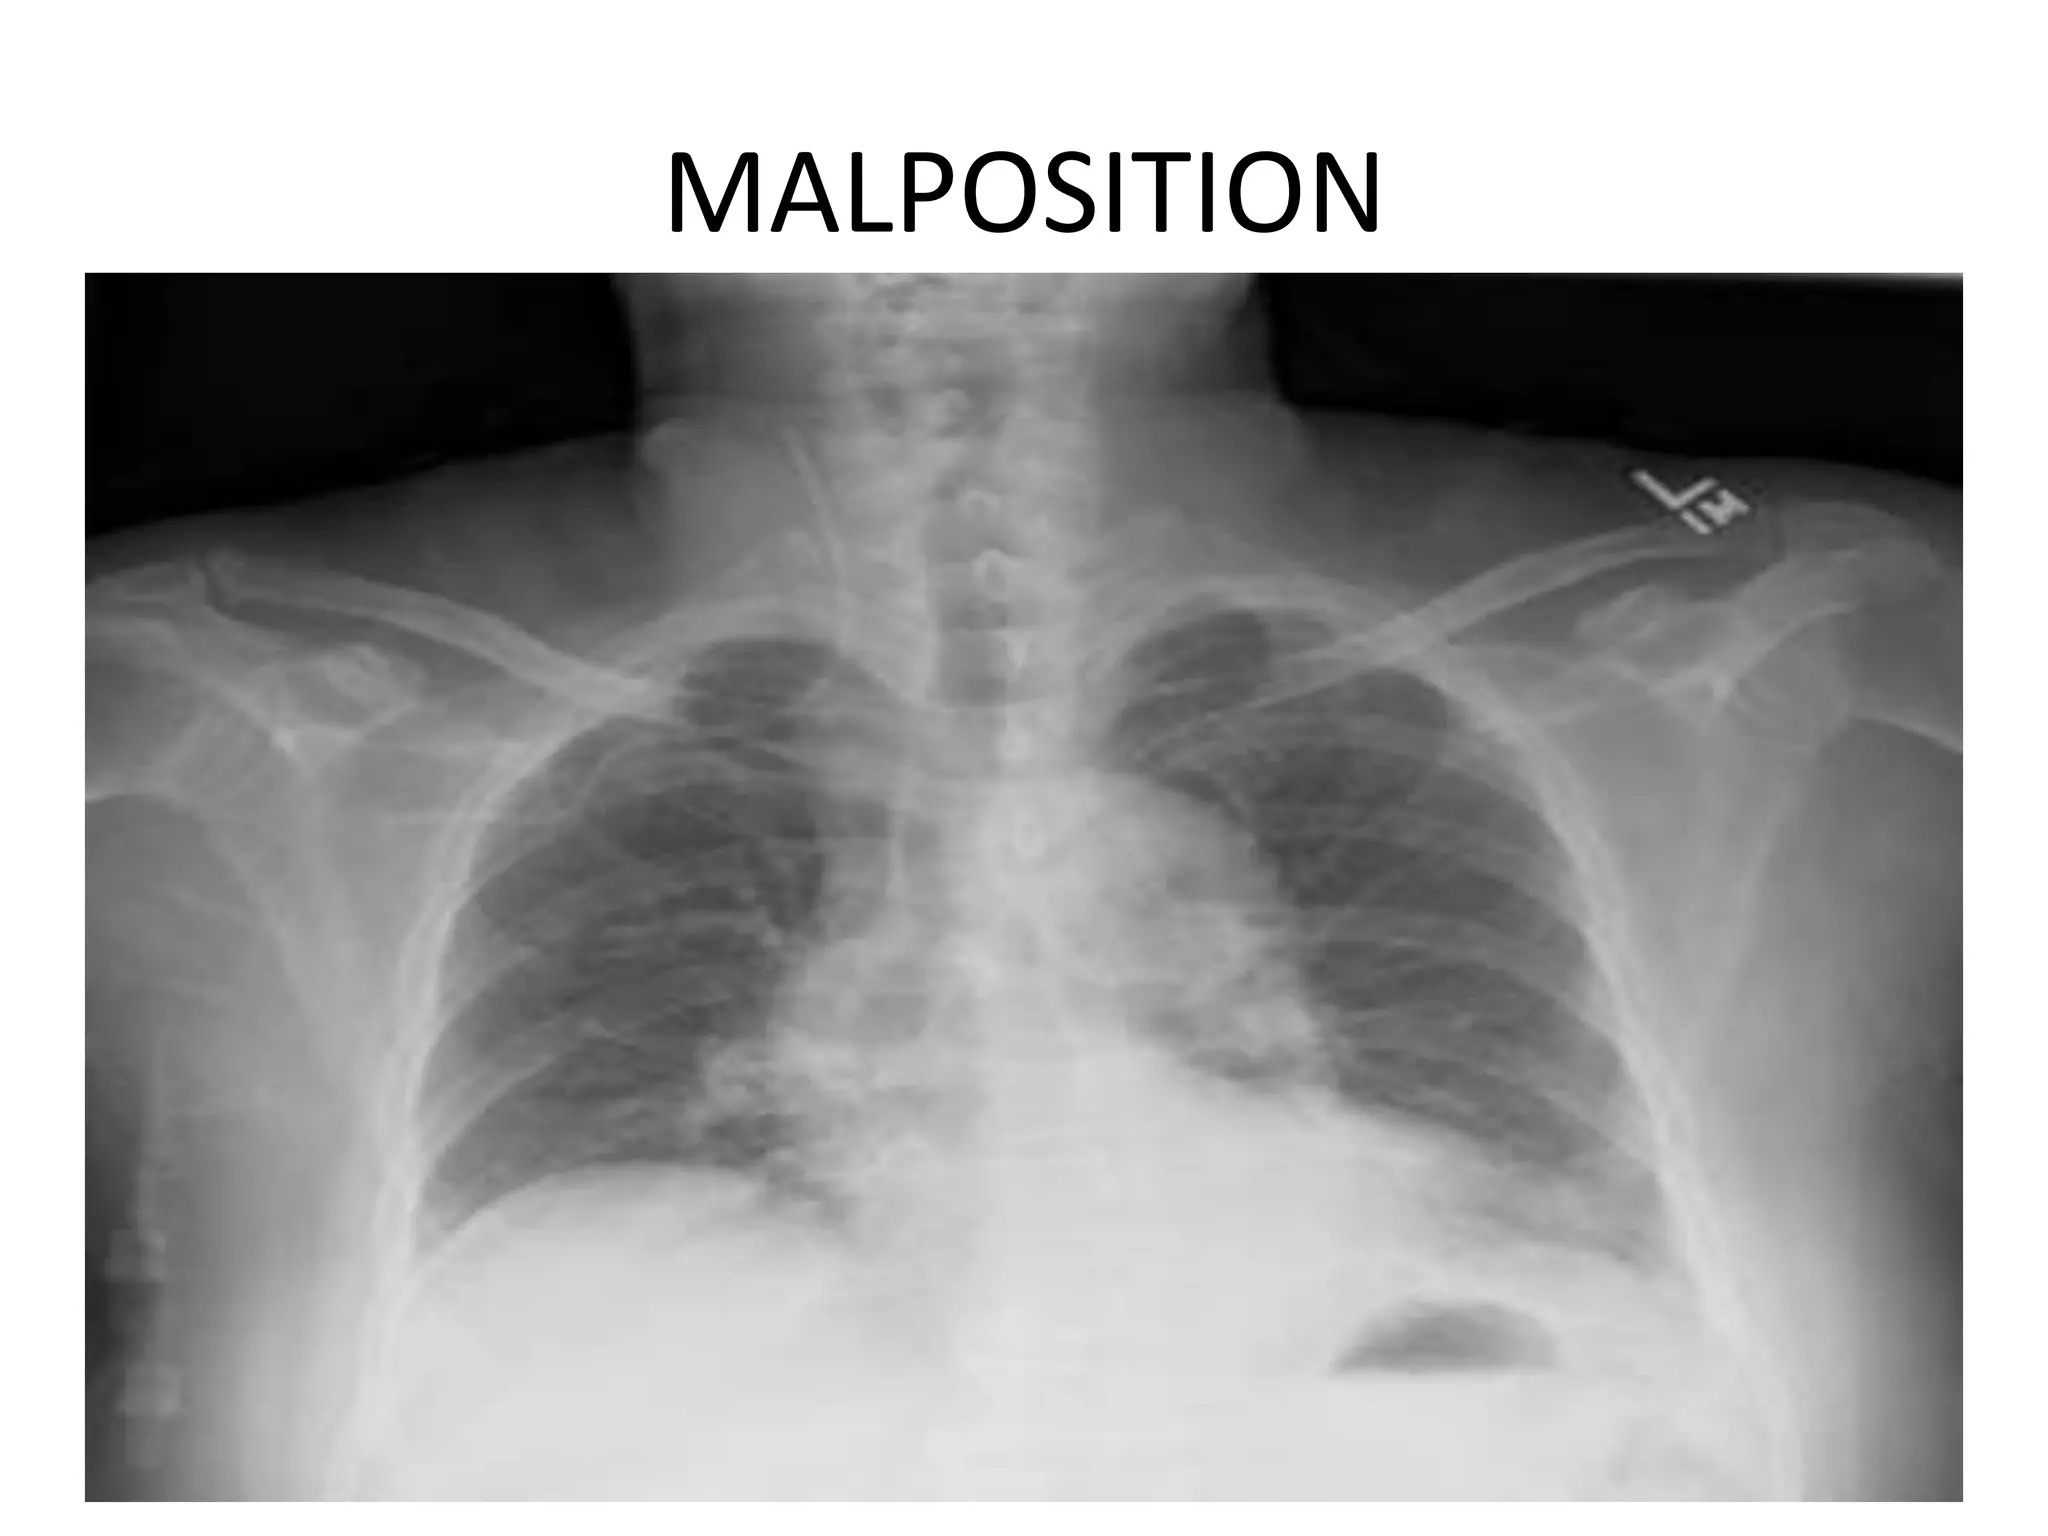

MALPOSITION